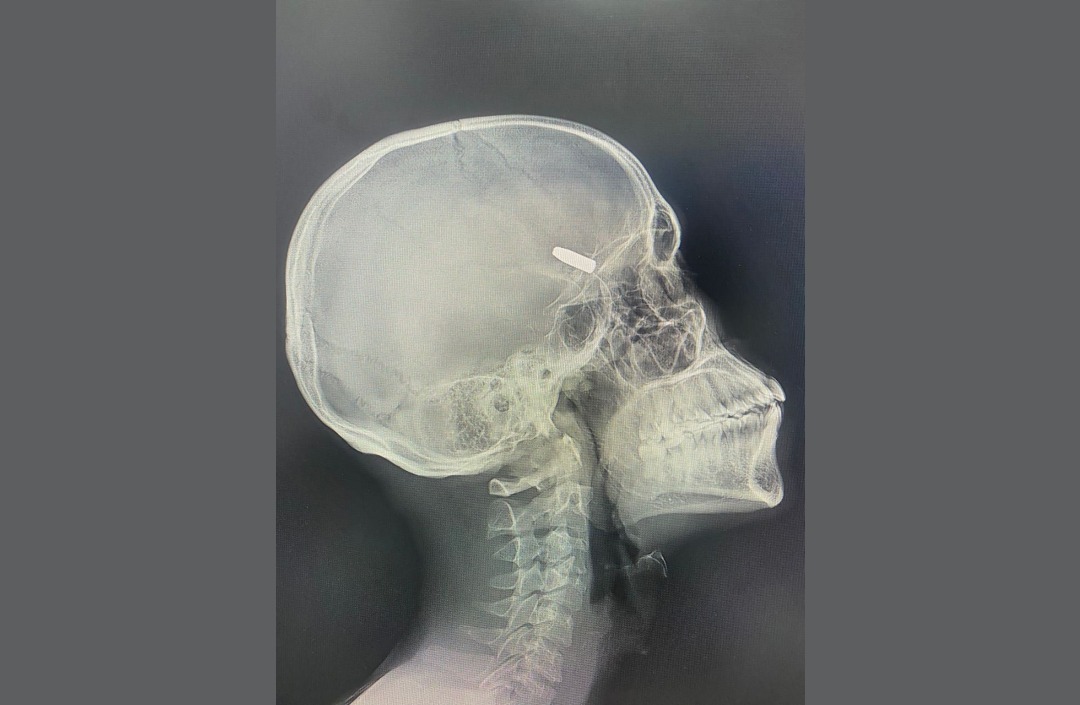

Extraction réussie d’une balle logée dans la tête d’un patient au CHTT/CNSS

En moins d’un mois après son inauguration, le Centre Hospitalier Tshisekedi Tshilombo (CHTT) de la CNSS ouvre une ère médicale inédite dans la région du Grand-Katanga. Sa troisième intervention neurochirurgicale majeure vient d’être couronnée de succès. Un défi d’une extrême délicatesse ; extraire une balle logée dans la tête d’un patient sans endommager nerfs ou fonctions cérébrales.

Sous la direction experte du Docteur KABULO Dieu-Merci, chaque geste a été minutieusement optimisé, mettant ainsi en avance son adresse chirurgicale. Et malgré les risques élevés, l’opération a été un succès, une victoire pour nos spécialistes et un tournant pour notre région.

Confronté à la nécessité d’agir avec une précision millimétrique, l’équipe de neurochirurgie a fait preuve d’un savoir-faire remarquable. Résultat, le patient se réveille sans séquelles et hors de danger.